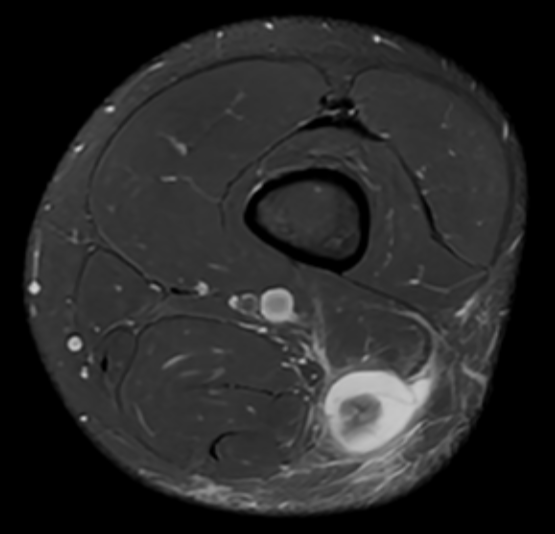

3. Torn long head of biceps femoris - BAMIC grade 4